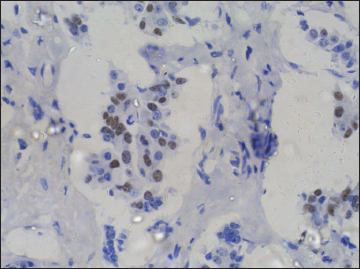

A 52 year-old nonsmoker, alcoholic male patient with spinocerebellar ataxia as comorbidity, presented in November 2016, with a complaint of progressive dysphagia of 2 months duration. Upper gastrointestinal endoscopy showed circumferential growth in lower-third of the esophagus with luminal narrowing. Computed tomography (CT) of thorax showed 13-mm thick circumferential mural thickening involving long segment of the lower esophagus causing marked luminal narrowing [Figure 1]. There was 3.5 cm × 2.5 cm mass in the subcarinal region, compressing esophageal lumen along with the few perigastric nodes [Figure 2]. Positron-emission tomography (PET)-CT showed intense fluoro-deoxy-glucose (FDG) avid thickening in the lower third of esophagus with FDG avid lower paratracheal, subcarinal, and perigastric nodes. Biopsy from the esophagus was done which was suggestive of moderately differentiated squamous-cell carcinoma [Figure 3]. The patient received neoadjuvant chemoradiation with 41.4Gy/23#/5 weeks by 3D-conformal radiation therapy technique along with five cycles of chemotherapy with injection paclitaxel 60 mg/m2 and injection carboplatin area under the curve 2 weekly. There was significant response to the treatment. Subsequently, the patient underwent thoracoscopic esophagectomy with gastric pull with feeding jejunostomy in February 2017. Histopathology showed minimal residual squamous-cell carcinoma of the esophagus with subcarinal node showing features of neuroendocrine tumor [Figure 4]. Subsequently, immunohistochemistry (IHC) was done to confirm the histopathological findings. IHC in esophageal blocks showed strong positivity for CK 5/6 [Figure 5], P63 [Figure 6], and epithelial membrane antigen [Figure 7] in tumor and surface epithelium with Ki67-30% [Figure 8], suggestive of residual small focus of squamous-cell carcinoma. IHC on subcarinal node was negative for CK5/6 and P63, strongly positive for synaptophysin [Figure 9] plus chromogranin [Figure 10], and weekly positive for CK7 [Figure 11], CK20 [Figure 12], and CDX2 [Figure 13]. Ki67 index was 4% [Figure 14], overall suggestive of atypical carcinoid tumor. There was no symptom related to endocrine overactivity or carcinoid syndrome. Follow-up PET-CT was normal, and hence the patient was kept on close follow-up, but at the time of writing the paper, the patient was untraceable.

| Figure 14 Immunohistochemistry on subcarinal node showing weak positivity for Ki-67